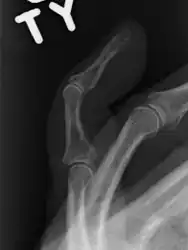

A mallet finger without an associated fracture